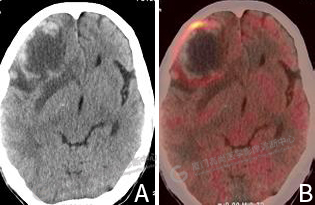

圖2:A CT圖像,右側(cè)額葉見一混雜密度腫塊影,形態(tài)欠規(guī)則,其內(nèi)伴低密度壞死區(qū)。B PET/CT融合圖像,病灶邊緣局限性代謝增高。

雙肺見多發(fā)結(jié)節(jié)影,大者位于左肺下葉外基底段,大小約0.9×0.8cm,F(xiàn)DG攝取明顯增高,SUVmax 7.7。右側(cè)額葉見一混雜密度腫塊影,大小約5.1×4.1cm,形態(tài)欠規(guī)則,其內(nèi)密度不均,伴低密度壞死區(qū),邊緣見斑片、條片狀高密度影,實質(zhì)部分FDG攝取呈環(huán)形增高,SUVmax 8.3,周圍見片狀水腫帶(圖2)。